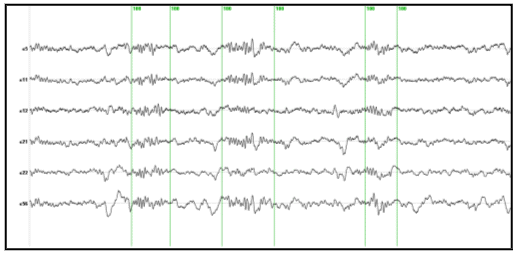

Nocturnal EEG was collected from 64 electrodes in an epileptic patient using a sampling rate of 200 Hz. Electrodes were positioned according to the extended 10/20 system as indicated in Figure 2. Preprocessing consisted in a nearest neighbour based interpolation of electrode P5 and transformation of the data to the average reference. Sleep spindles were automatically selected from the stage 2 of sleep using a semiautomatic procedure described below.

To select sleep spindles we used the concept of spectral envelope. A set of two frontal, two central and two parietal EEG channels were a priori selected. The EEG at these channels was narrowly band filtered within two frequency ranges (11-13 Hz and 13-15 Hz). The band-pass filter was based on a simple direct and inverse Fourier transform with pruning of undesired frequencies. The envelope was computed for the filtered signals in both ranges by transforming the filtered data to z-scores followed by a Hilbert transform. The Hilbert transform returns the analytic signal whose magnitude is the complex envelope of the original signal. Spindles were marked if their envelope showed the characteristic waxing and waning properties characteristic of sleep spindles in frontal, central or parietal derivations. Typical examples of the signals and their envelopes are shown in Figure 3.

EEG segments containing two or more consecutive spindles were selected for analysis. The goal was to study the whole spatio-temporal distribution of the spindle generators not only at the time of spindles but also between spindles. The rational to analyze the inter spindles interval derives from the experimental observation that in rats cortical spindles tend to follow hipocampal ripples (Siapas and Wilson 1998).  It has been suggested that the hippocampal circuitry may be biasing the initiation of the spindle–ripple episodes either through direct anatomical projections (Jay and Witter, 1991) or indirectly through neural systems such as the entorhinal cortex or the basal ganglia. We were therefore interested in observing if temporal lobe structures were activated during the inter-spindles interval.

Figure 4 shows some original EEG traces for a segment where three spindles were identified. The vertical markers indicate the timing of the spindles as detected from their spectral envelope. Figure 5 (lower panel) shows the modulus of the MaSTiF decomposition, d(t,w), for the EEG segment shown in Figure 4 and its associated simplicity test map (Figure 5, upper panel). The simplicity map indicates the time frequency points where the map seems to be produced by a simple generator configuration, i.e., all sensors have approximately the same phase for the given time-frequency pair.

Figure 4. Original EEG traces with markers (green vertical lines) indicating the spindles identified from the spectral envelope.